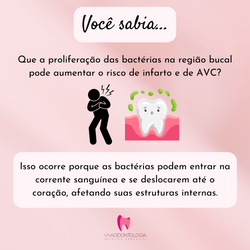

Curiosidades.jpg |  uso de máscara dentista post instagram (5).png |  uso de máscara dentista post instagram (2).png |

uso de máscara dentista post instagram (3).png |  uso de máscara dentista post instagram (6).png |  uso de máscara dentista post instagram (9).png |